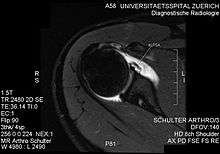

ALPSA lesion

An ALPSA (anterior labral periosteal sleeve avulsion) lesion is an injury at the front of the shoulder associated with shoulder dislocation.

The shoulder joint is made up of the glenoid and humeral head. The humeral head is ball shaped but the glenoid is more dish shaped than cup shaped. To aid stability of the joint, the glenoid has a soft tissue bumper around its edge (the labrum) which acts as a bumper preventing dislocation of the head from the glenoid.

The anterior (front) labrum can peel off the glenoid resulting in a Bankart lesion. When the periosteum (fibrous tissue surrounding bone) peels off as well this is called an ALPSA lesion. When this happens the labrum (bumper) falls away and rolls up. It normally falls medially and downwards.